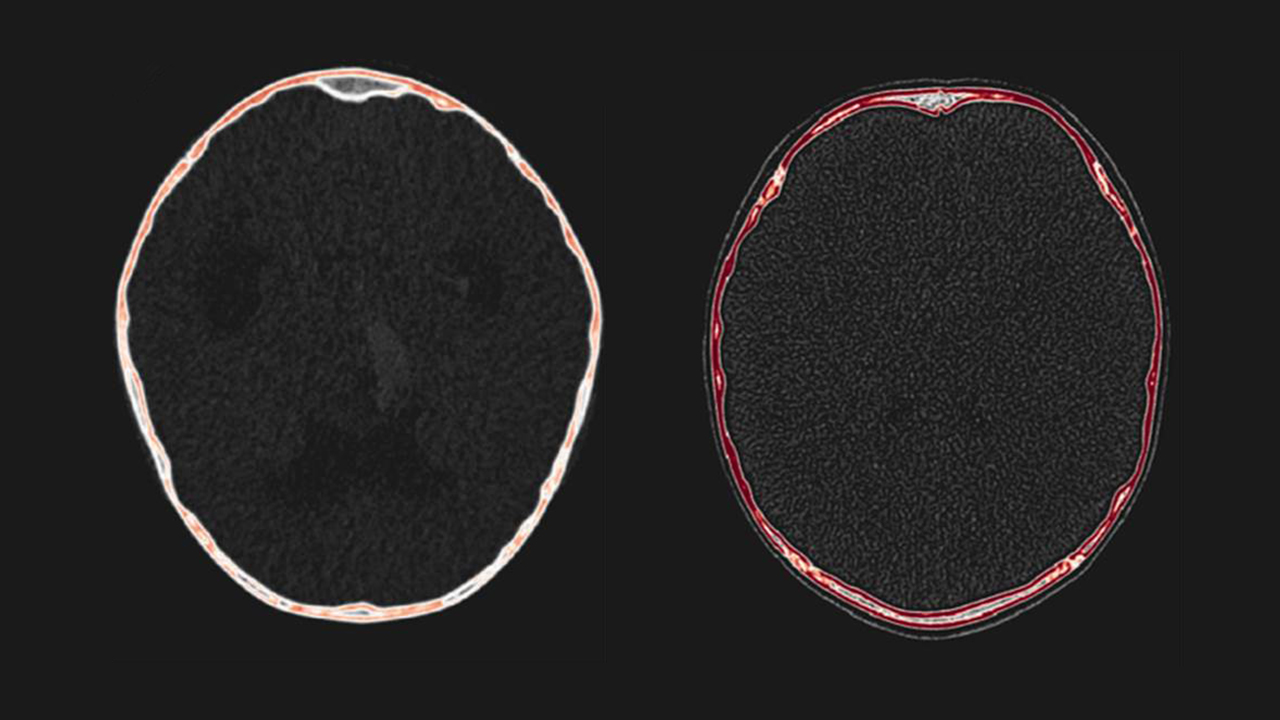

Dr. Porras’ latest work aims to offer doctors a clearer perspective on the presence of intracranial pressure, based on bone density and thickness — two measures that can be taken through a simple CT scan.

“I noticed when I was going through these surgeries that when the brain has pressure, the bone has very subtle changes that you can only see when you operate on the kid. You can actually see that the density of the bone decreases, but this is something that is very, very hard to see because of the subtlety of the changes and their dependence on the specific age of the patients,” Dr. Porras explains.

To understand the connection between these variables and intracranial pressure, Dr. Porras and his team conducted a retrospective study to quantify cranial bone thickness and mineral density from CT images of children with chronic intracranial pressure. They compared these to data from children without the condition and found that in kids with chronic intracranial pressure, bone density was lower, and bones were typically thicker.

Through this work, the team proved that density and thickness anomalies can be used to identify intracranial pressure. From there, Dr. Porras and his team began the work of creating a normative model of bone density and thickness for every age and sex that would give doctors a reference to compare their measurements to. The quickest and most effective method to accomplish this was through artificial intelligence and machine learning.